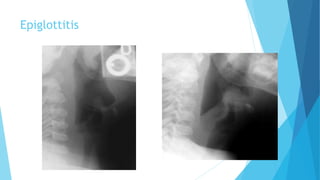

Soft tissue X-ray of neck

 Anterior-posterior view is normal

 Lateral view: ***THUMB PRINT***

 swelling epiglottis/ary epiglottic folds

 fullness of the valleculae

 ballooned hypopharyx

 assess the retropharyngeal space

Epiglottitis

Acute epiglottitis: swan neck